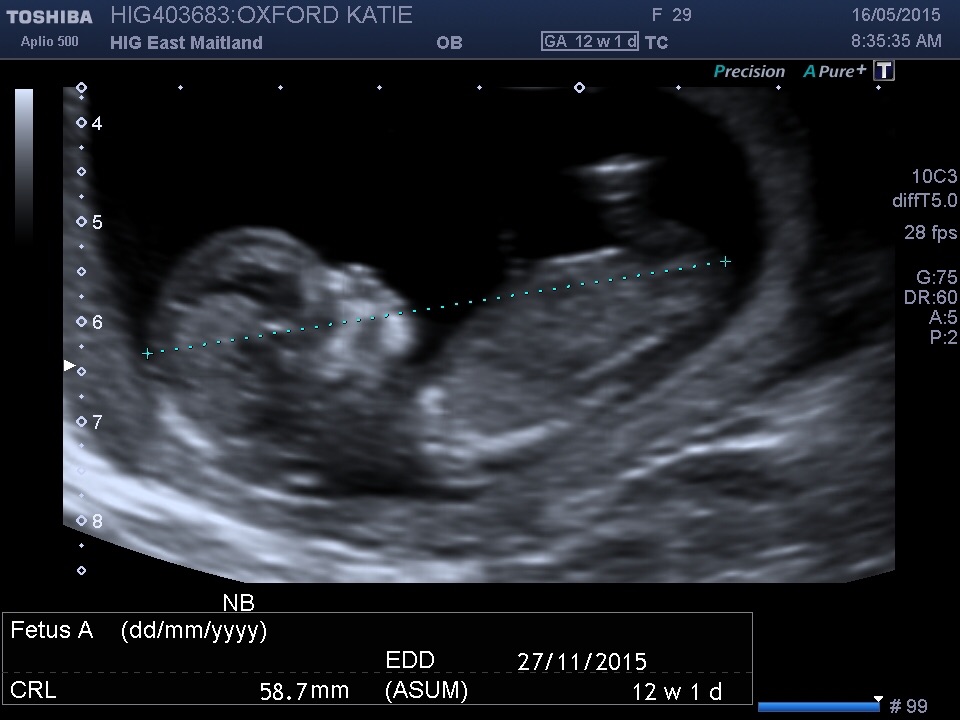

That scan would have been your dating scan! Which would have used how big it was to date it haha! So it will be the average size of a baby that exact age :-) I think he/she looks adorable and the perfect size ❤️

This was last Saturday at 12w3d. My best friend is a sonographer so she got me in. She wanted to try and guess if baby is a boy or girl. When we go by the nub theory it's a boy! She said she's pretty confident. When she was pregnant She knew she was having a girl this early so we will see if she's right!!